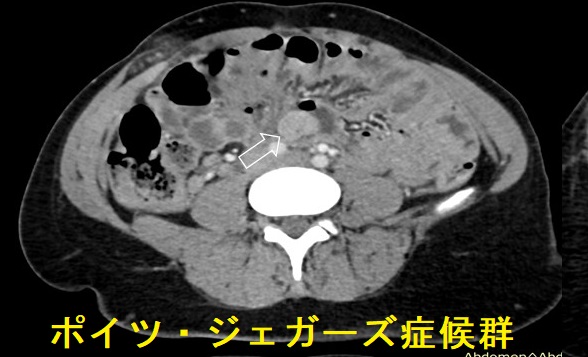

ポイツ・ジェガーズ症候群(Peutz-Jeghers症候群)は、常染色体性優性遺伝による癌抑制遺伝子Liver Kinase B1 (LKB1 or STK11)の機能喪失型変異が原因です。

- 小腸ポリポーシス(過誤腫ポリープ);1~3cmのポリープが小腸(特に空腸)に多発。有茎性・分葉状が多く、高頻度に再燃性腸閉塞・腸重積。慢性的な腸出血(下血)

- 悪性腫瘍の合併(50歳までに30%、70歳までに80%)

消化器癌が最多(60%);食道、胃、小腸、大腸、膵臓

甲状腺癌(Thyroid. 2011 Nov;21(11):1273-7.)

甲状腺癌の合併

ポイツ・ジェガーズ症候群(Peutz-Jeghers症候群)に合併する甲状腺分化癌(甲状腺乳頭癌・甲状腺濾胞癌)は、通常のものと比べて悪性度が高いとされます(Exp Clin Endocrinol Diabetes. 2009 May;117(5):234-9.)。